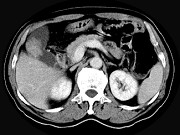

- 单项选择题男,45岁, 右季肋区疼痛,Murphy征阳性, B超提示胆囊息肉,CT所见如图, 最可能的诊断为 ( )